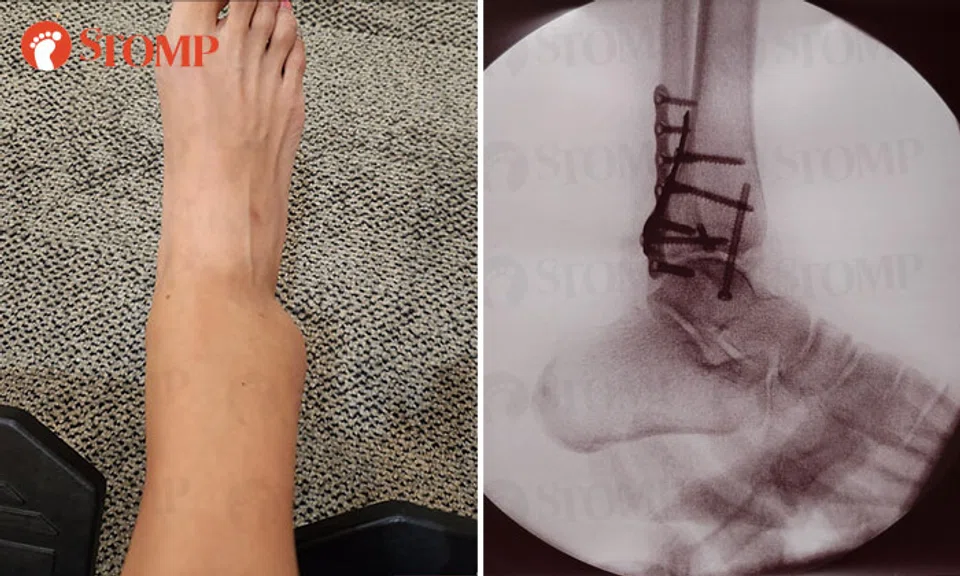

The Stomper had to undergo surgery following the injury. She shared X-ray images showing several screws implanted in her ankle.

She is currently in a cast and is not allowed to bear any weight on her ankle.